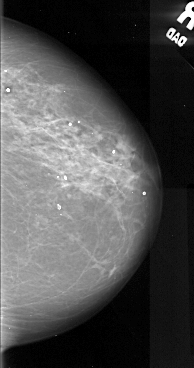

A_1049_1.RIGHT_CC

RIGHT_CC LINES 5146 PIXELS_PER_LINE 2716 BITS_PER_PIXEL 16 RESOLUTION 42 NON_OVERLAY